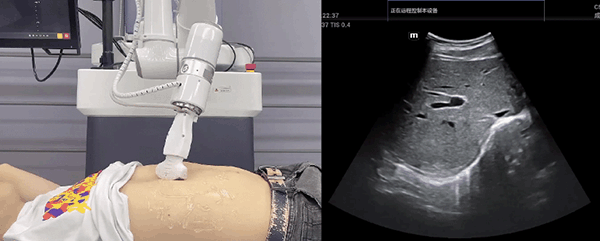

艾利特機(jī)器人末端搭載超聲探頭,可以對(duì)淺表小器官和外周血管、腹部(肝、膽、胰、腎等器官)進(jìn)行超聲檢查。

普羅超聲聚焦治療機(jī)器人

目前,艾利特機(jī)器人在生物醫(yī)藥、醫(yī)療健康領(lǐng)域的賦能已有顯著進(jìn)展,艾利特協(xié)作機(jī)器人應(yīng)用場景覆蓋了臨床試驗(yàn)、試管檢測、拭子采集、試管搬運(yùn)、熒光檢測、康復(fù)治療、超聲掃查、導(dǎo)診、消毒、微創(chuàng)治療、針灸刮痧等。